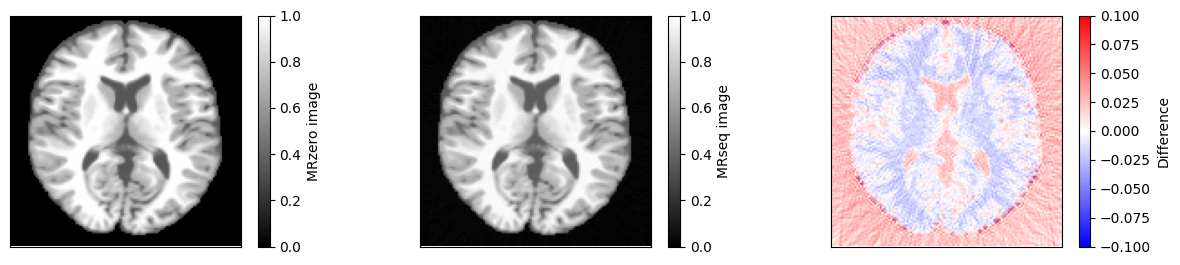

Compare to theoretical model#

We can now compare the result to a simulation using the idealized signal model for spoiled gradient echo sequences. First, we need to calculate \(T2^*\) using \(1/T2^* = 1/T2 + 1/T2'\).

im = ax[0].imshow(idat_model, vmin=0, vmax=1, cmap='gray')

fig.colorbar(im, ax=ax[0], label='MRzero image')

im = ax[1].imshow(idat, vmin=0, vmax=1, cmap='gray')

fig.colorbar(im, ax=ax[1], label='MRseq image')

im = ax[2].imshow(idat - idat_model, cmap='bwr', vmin=-0.1, vmax=0.1)

fig.colorbar(im, ax=ax[2], label='Difference')

relative_error = np.sum(np.abs(idat - idat_model)) / np.sum(np.abs(idat_model))

print(f'Relative error {relative_error}')

assert relative_error < 0.05

Relative error 0.03551841384450442